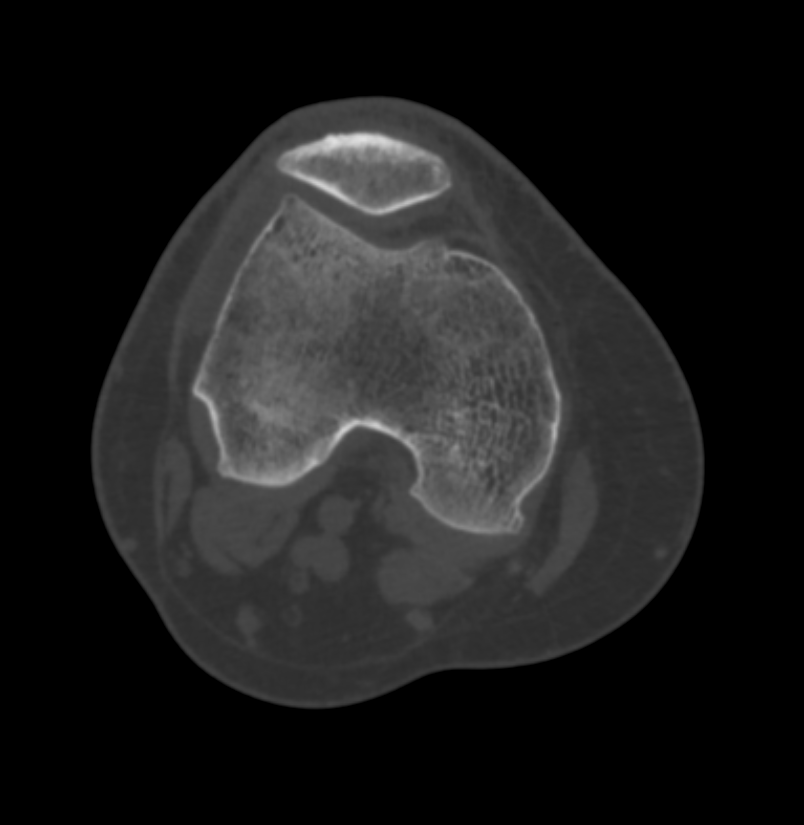

A tomografia em questão é o exame que analisa a articulação do joelho e os ossos, como fêmur, tíbia, patela e fíbula.